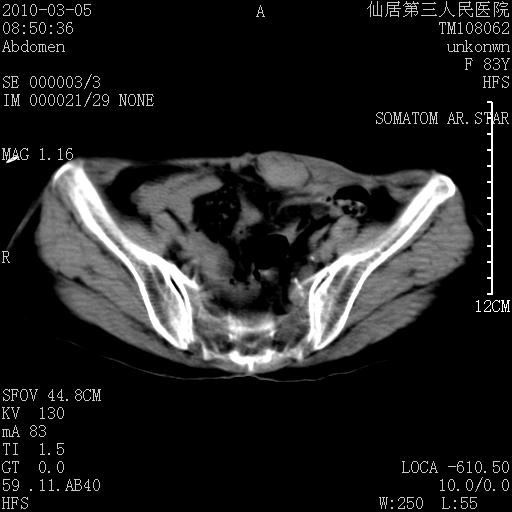

标题: CT24879:腹直肌病变。在线等。

女性,83y,腹痛一周。

考虑:左侧腹直肌神经纤维瘤可能

神经纤维瘤—伴有出血?

有无外伤,血肿或韧带样瘤

考虑左侧腹直肌血肿,肿瘤性病变待排。

增强看看,mfh可能性大,次之可考虑血肿、bfh、转移瘤、神经纤维瘤、侵袭性韧带样纤维瘤等。肝内钙化灶,右肾结石。

支持腹壁纤维肉瘤

血肿,纤维瘤,子宫内膜异位都有可能。